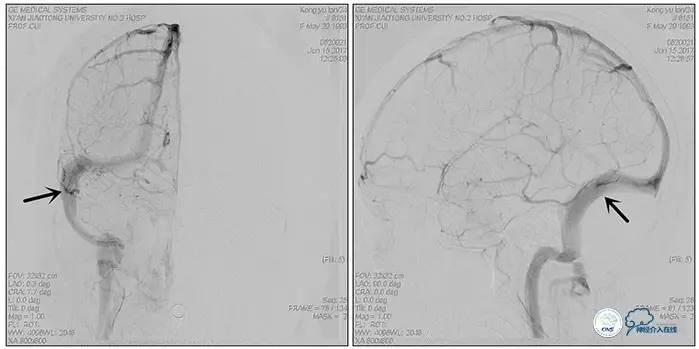

术中右侧ICA造影

右侧ICA斜位及窦内造影

右侧ICA斜位

窦内造影及路图

术中测压:

远端:520mmH2O,

近端:190mmH2O。

治疗方案:

1、8mm×40mm , EverCross球囊扩张;

2、8mm×40mm,Protégé自膨支架成形术。

术后右侧ICA造影

术后远、近端压力差为:0

术后右侧ICA斜位